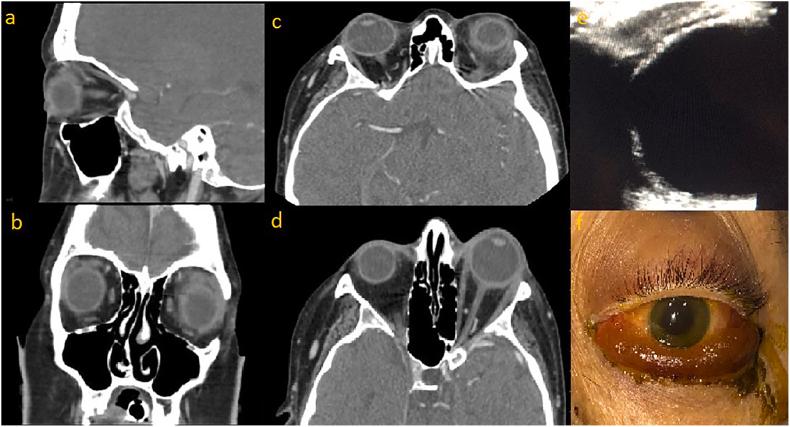

A 33-year-old female presented to the Emergency Department (ED) with acute liver failure. During the first week of her hospital admission, she developed unilateral eyelid swelling and proptosis, prompting a consult to ophthalmology. Additional physical examination revealed significantly decreased visual acuity, extraocular muscle restriction, afferent pupillary defect, and increased intraocular pressure. Computed tomography (CT) and ultrasound confirmed the diagnosis of intraorbital hemorrhage. Aggressive management in the form of lateral canthotomy, cantholysis, and septolysis was unable to be performed due to the patient's multiple comorbidities outweighing the potential benefits.

This rare phenomenon is unique from previous existing literature in that the timing of the incident limited the therapeutic options for this patient, additional imaging in the form of ultrasound was utilized in the work-up, and to our knowledge this is the second case of spontaneous orbital hemorrhage as a complication of disseminated intravascular coagulation (DIC) caused by hepatic failure.